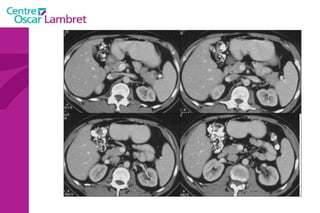

Foie Sous diaphragmatique 2 lobes 8 segments 2 pédicules vasculaires Ligaments

Le foie  pèse entre 1400 et 1600 g et mesure une dizaine de centimètres dans sa plus grande hauteur. L’apport sanguin hépatique est double : par la veine porte  par l’artère hépatique issue du tronc coeliaque.  L’ensemble veine porte- artère hépatique constitue, avec le canal cholédoque un pédicule hépatique.  La ramification de cette veine permet d’isoler 7 segments. Foie

Le sang quitte le foie par trois veines sus-hépatiques principales (droite, médiane et gauche) et des veines accessoires qui drainent le segment 1 (ou lobe de Spiegel. Les veines sus-hépatiques  principales délimitent 4 secteurs composés chacun de 1 à 2 segments :  latéral gauche (segments 2 et 3), paramédian gauche (segment 4), paramédian droit (segments 5 et 8)  latéral (ou postérieur) droit (segments 6 et 7) Elles se jettent dans la veine cave inférieure. Le Foie : 8 segments